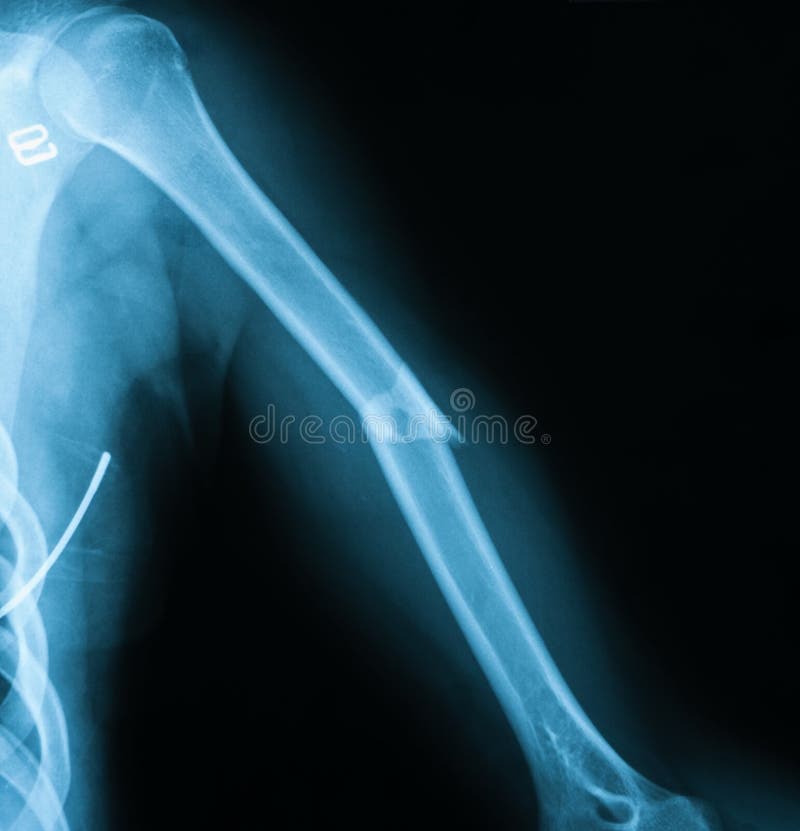

Humeral neck fracture, Xray Stock Image C039/3299 Science Photo Library

Xray Image of Humerus Fracture Stock Photo Image of fracture, joint 59188554 X Ray Humerus Fracture Front and side pictures show the swelling and bruising down the arm. Humeral shaft fractures are common fractures of the diaphysis of the humerus, which may be associated with radial nerve injury. A patient with a proximal humerus fracture. Most frequently humeral shaft fractures occur as a result of a direct blow to the upper arm (transverse fractures). Magnetic resonance. X Ray Humerus Fracture.